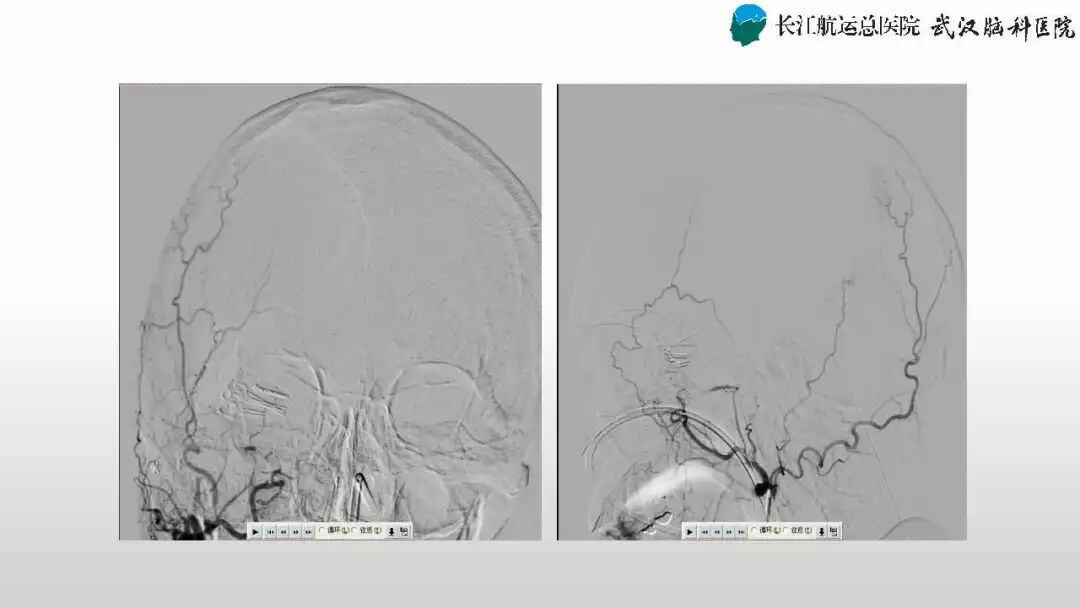

肖国民副主任医师:动静脉瘘手术